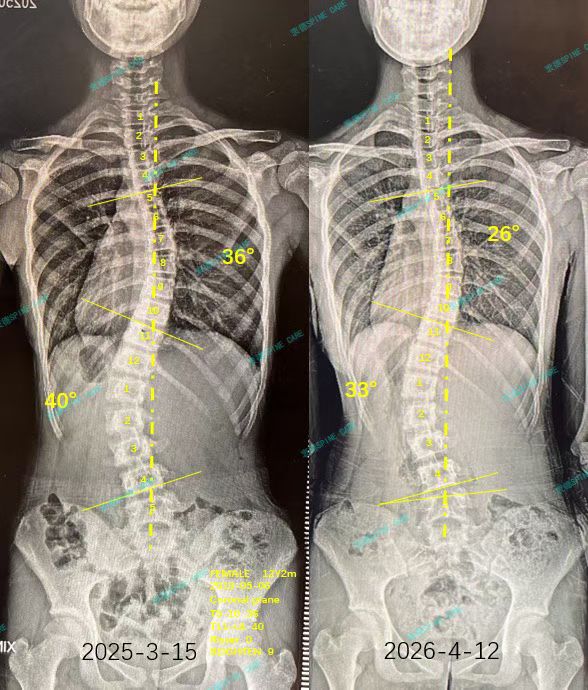

我是棠棠,腰椎旋转8度降至1度,腰弯40度降至33度,胸弯36度降至26度,体态改善~

不知不觉已经在衷德脊柱一年多了,从一开始的8度腰椎旋转已经到了现在的1度旋转了,非常棒。最近拍片发现我的腰弯角度从40度降到了33度,胸弯角度从36度降到了26度,杨博士说我坚持的很好,而且我的体态也比半年前拍片更加平衡了。

I have been working on my spine in Zhongde for more than a year without realizing it. I have gone from 8 degrees of lumbar rotation at the beginning to 1 degree of rotation now, which is very good. Recently, I found that my waist bend angle has dropped from 40 degrees to 33 degrees, and my chest bend angle has dropped from 36 degrees to 26 degrees. Dr. Yang said that I persisted very well, and my posture is more balanced than when I took x-ray half a year ago.